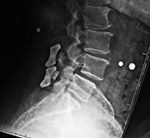

| 67 year-old woman with lower lumbar spinal stenosis. The patient is wearing a TLSO brace. |

76 year-old woman treated for degenerative spondylolysthesis at L4-5. The patient is wearing a TLSO brace. |